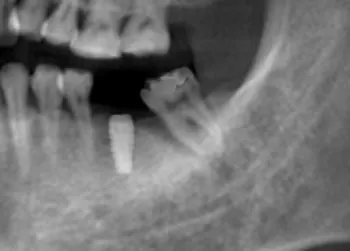

Case 2